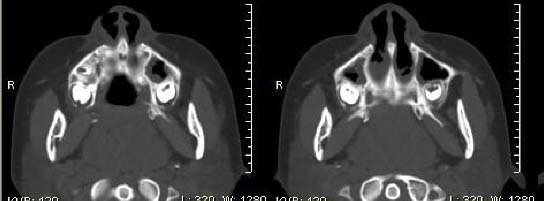

以下是引用随光逐影在2009-6-4 21:13:00的发言:[br]1)考虑鼻咽腺样体重度肥大。2)双侧鼻腔炎性改变。3)双侧上颌窦、双侧筛窦及左侧蝶窦炎症。

以下是引用zsl6918在2009-6-5 7:42:00的发言:[br]首先考虑鼻咽腺样体重度肥大,鉴别纤维血管瘤.强化有助明确.